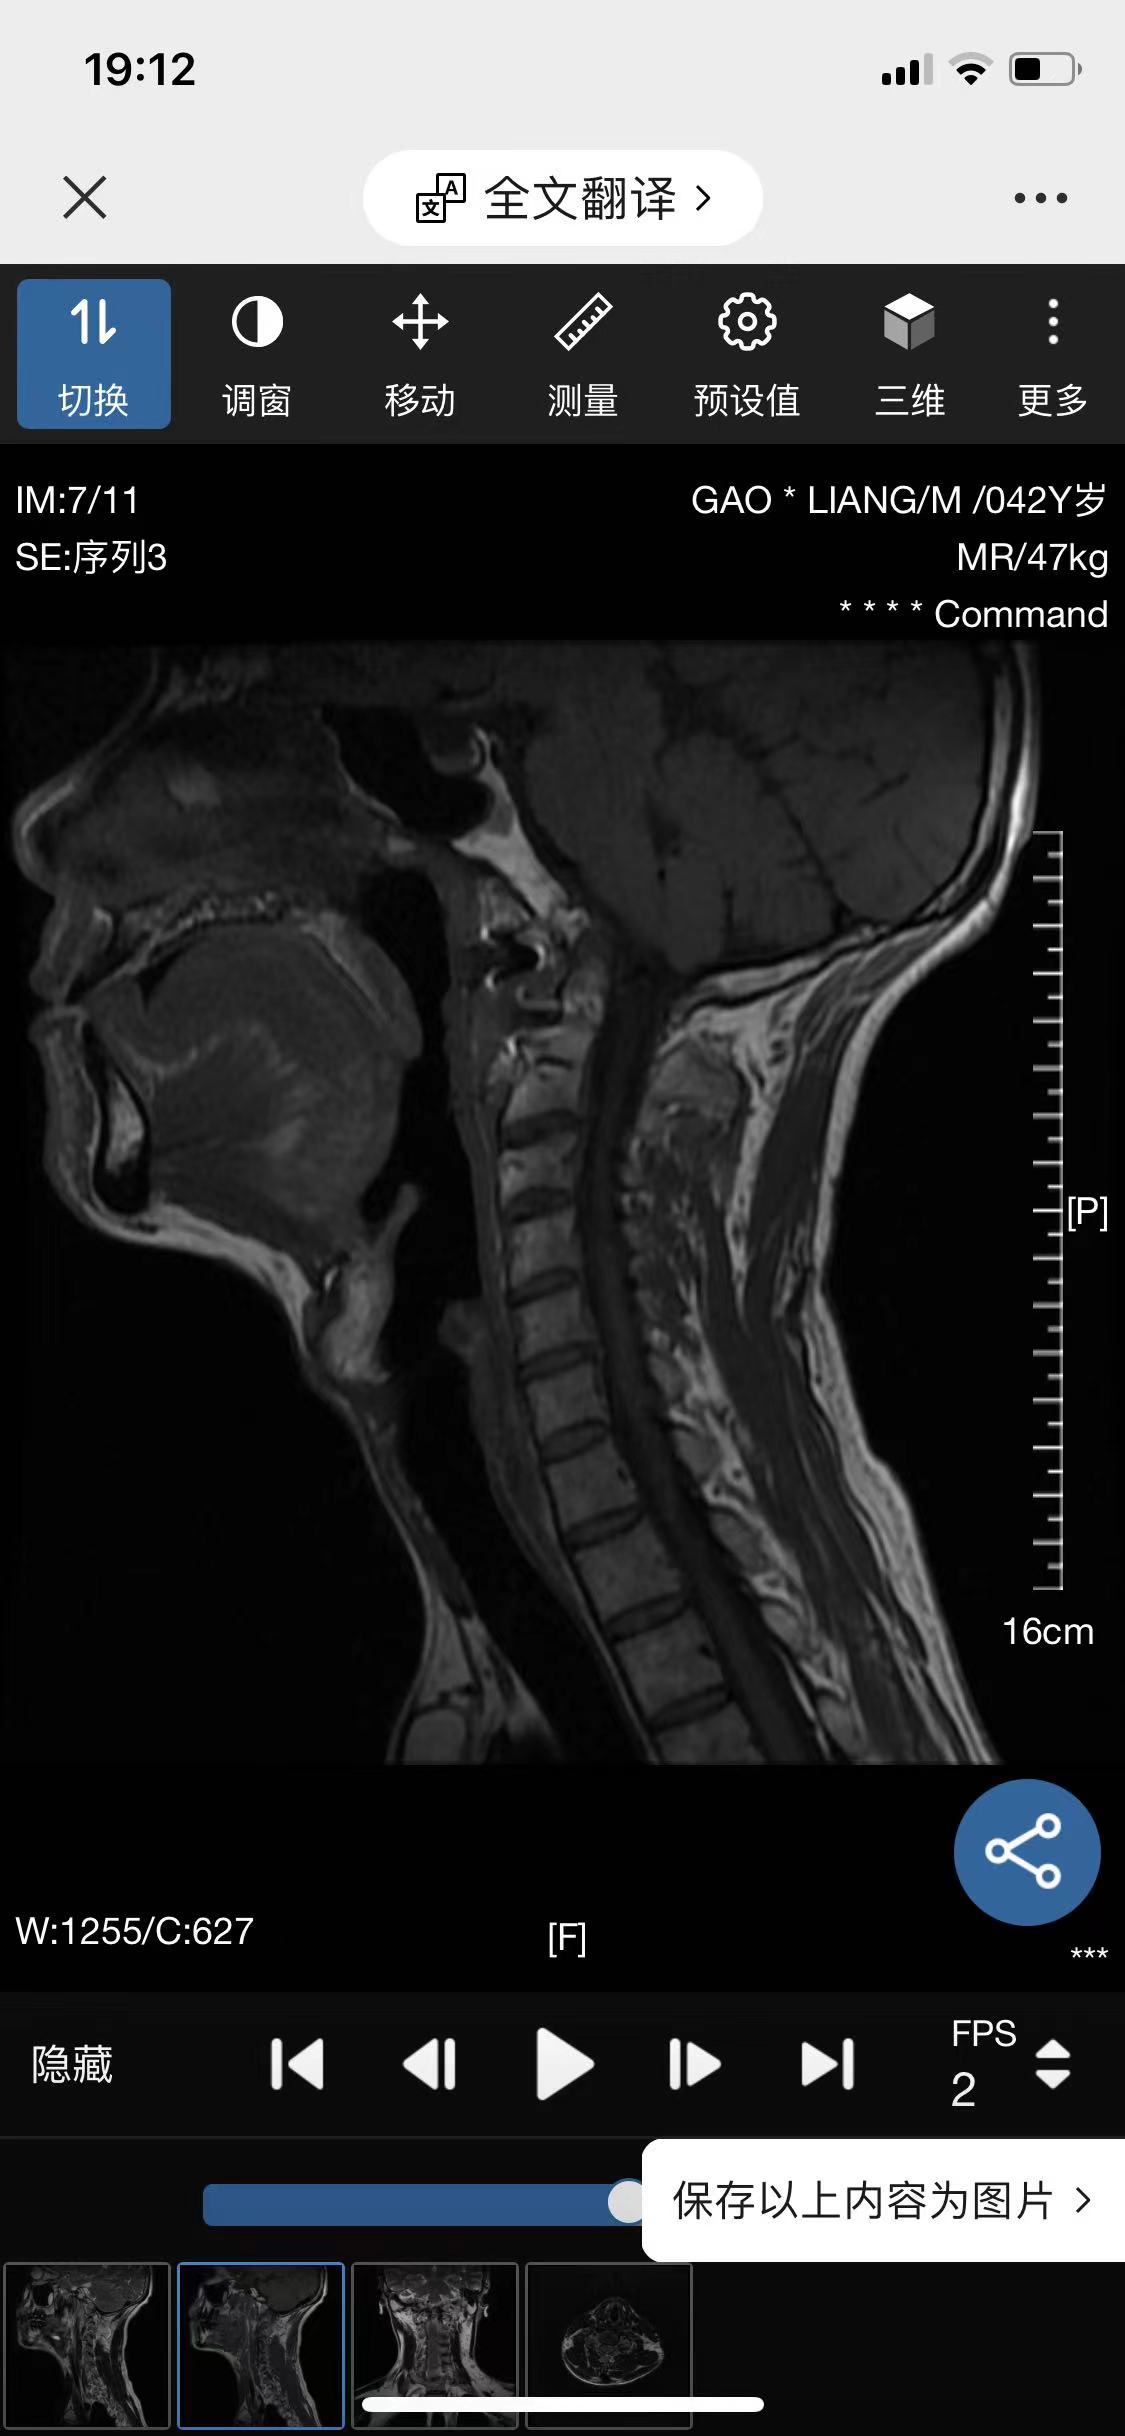

• 诊断:寰枢椎脱位

• 影像:

• 术后影像:

• 2024.04,半年复查。